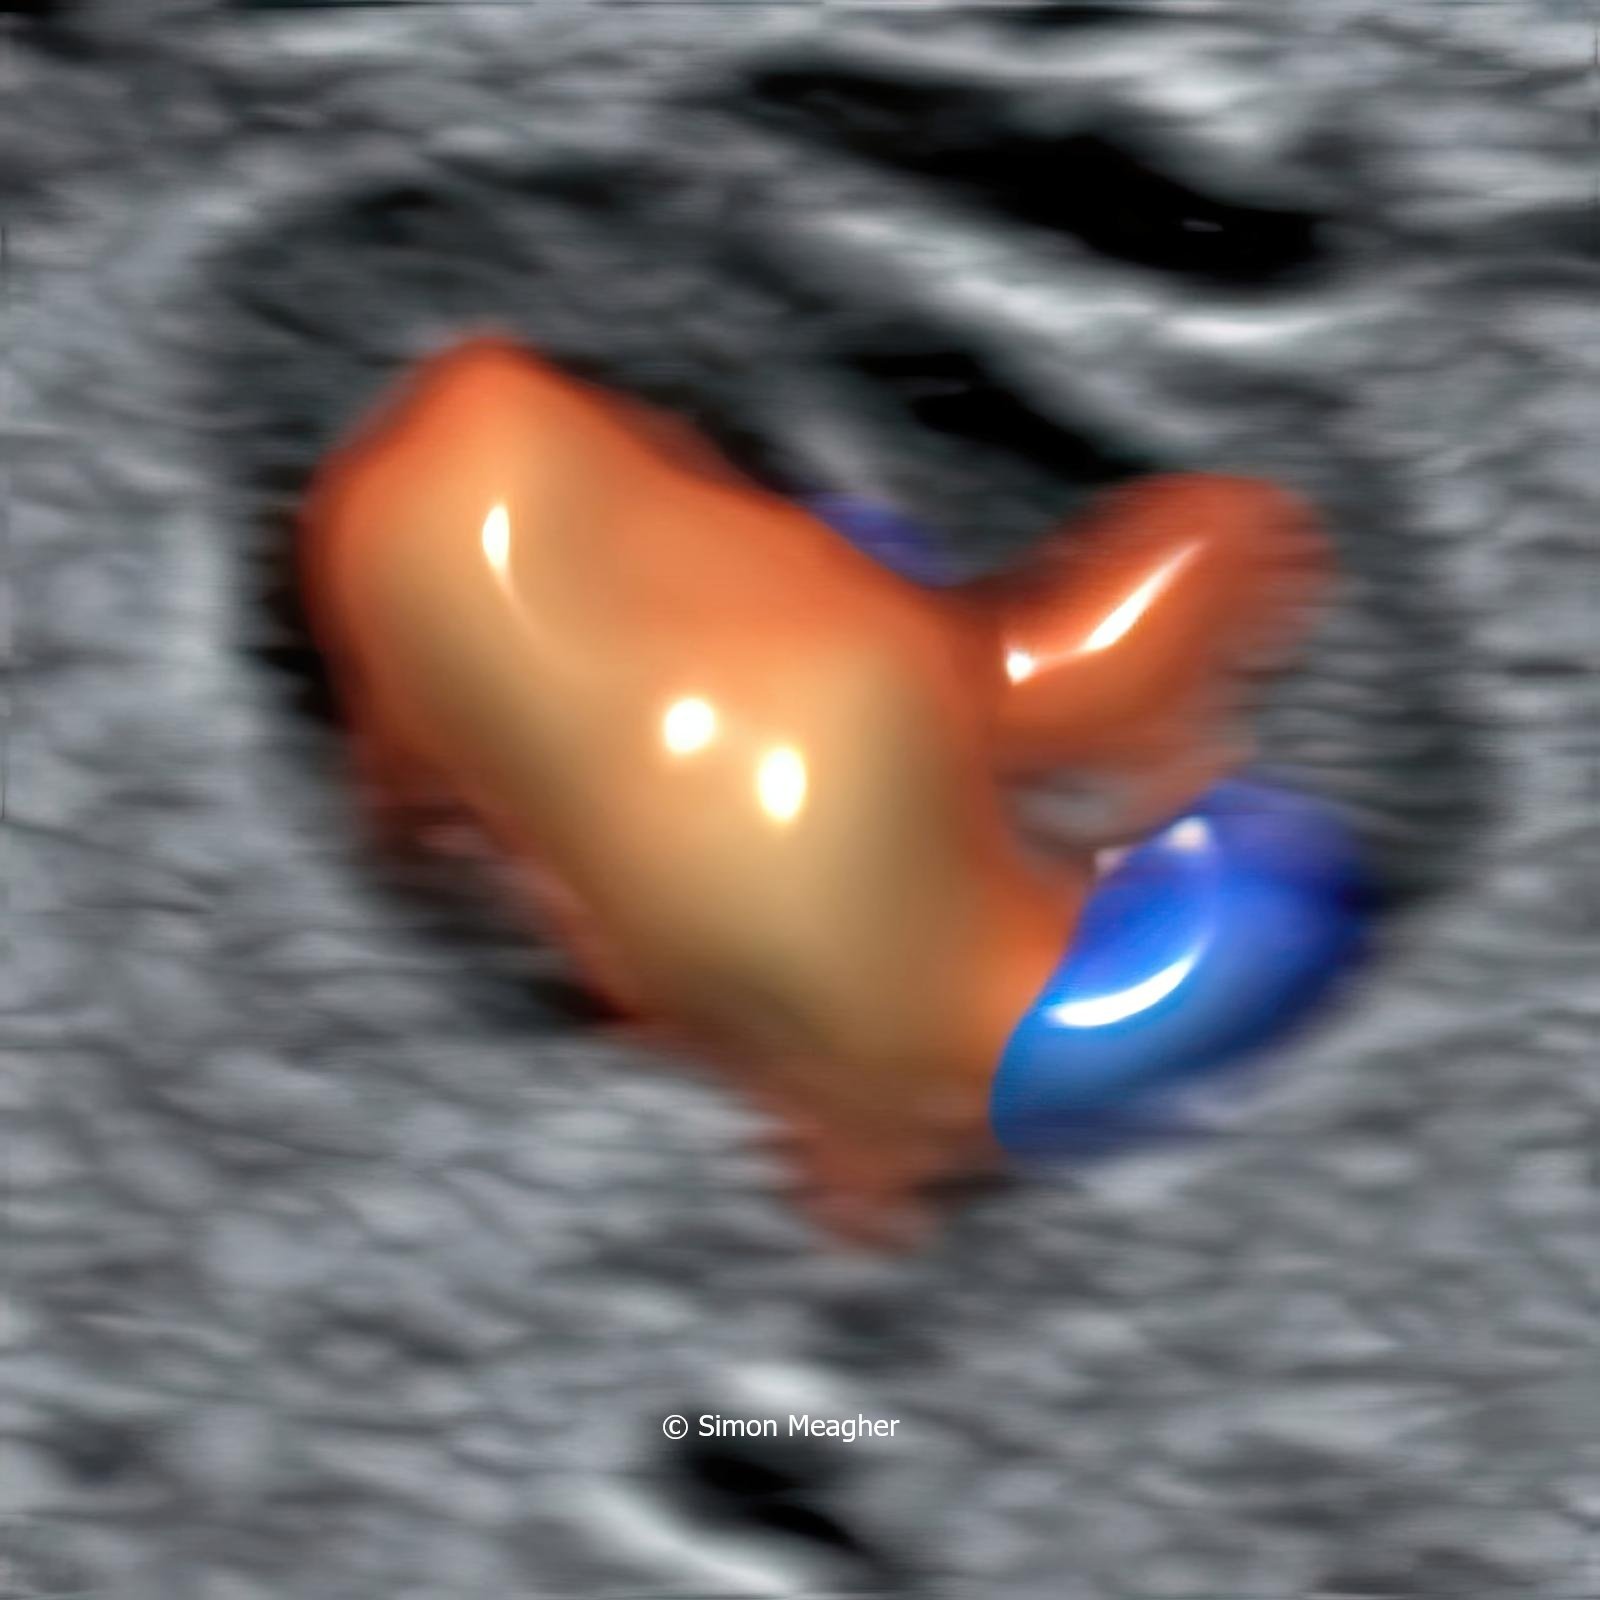

Join Professor Simon Meagher and leading experts for an intensive masterclass designed to transform your clinical practice.

This high-impact, one-day event delivers live scanning demonstrations, real-world case studies, and cutting-edge techniques across all trimesters.